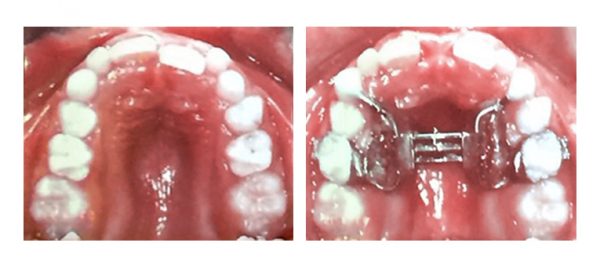

У вересні, в рамках академії безперервного навчання ортодонтів, Галина Матіюк прослухала курс

Dr.Marco Ross (Італія) “Early Orthodontic Treatment”. На знімках наведені випадки раннього лікування.